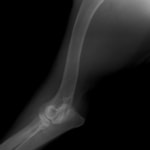

症例:柴犬 3歳

左後肢の完全挙上を主訴に来院されました。触診にて近位足根関節の過伸展を、レントゲン検査にて左足根関節周囲の軟部組織の腫脹、ストレス撮影によって距骨・踵骨と第4足根骨・中心足根骨間の脱臼および過伸展を認めました。

術中において、浅趾屈筋腱を剥離、内方へ牽引し、直接踵骨から第4足根骨までピンを挿入し(あらかじめ細いピンで下穴をあけておくとよい)、テンションバンドワイヤー法を併用し、関節軟骨の掻爬と海綿骨移植を実施しました。

術後レントゲン画像上に癒合が認められるまで約2ヵ月間は、運動を制限する必要があります。

術前正面像左関節の腫れ

左足根関節の軟部組織が腫脹しています。

術前正面像

術前側面像屈曲位

術前側面像伸展位